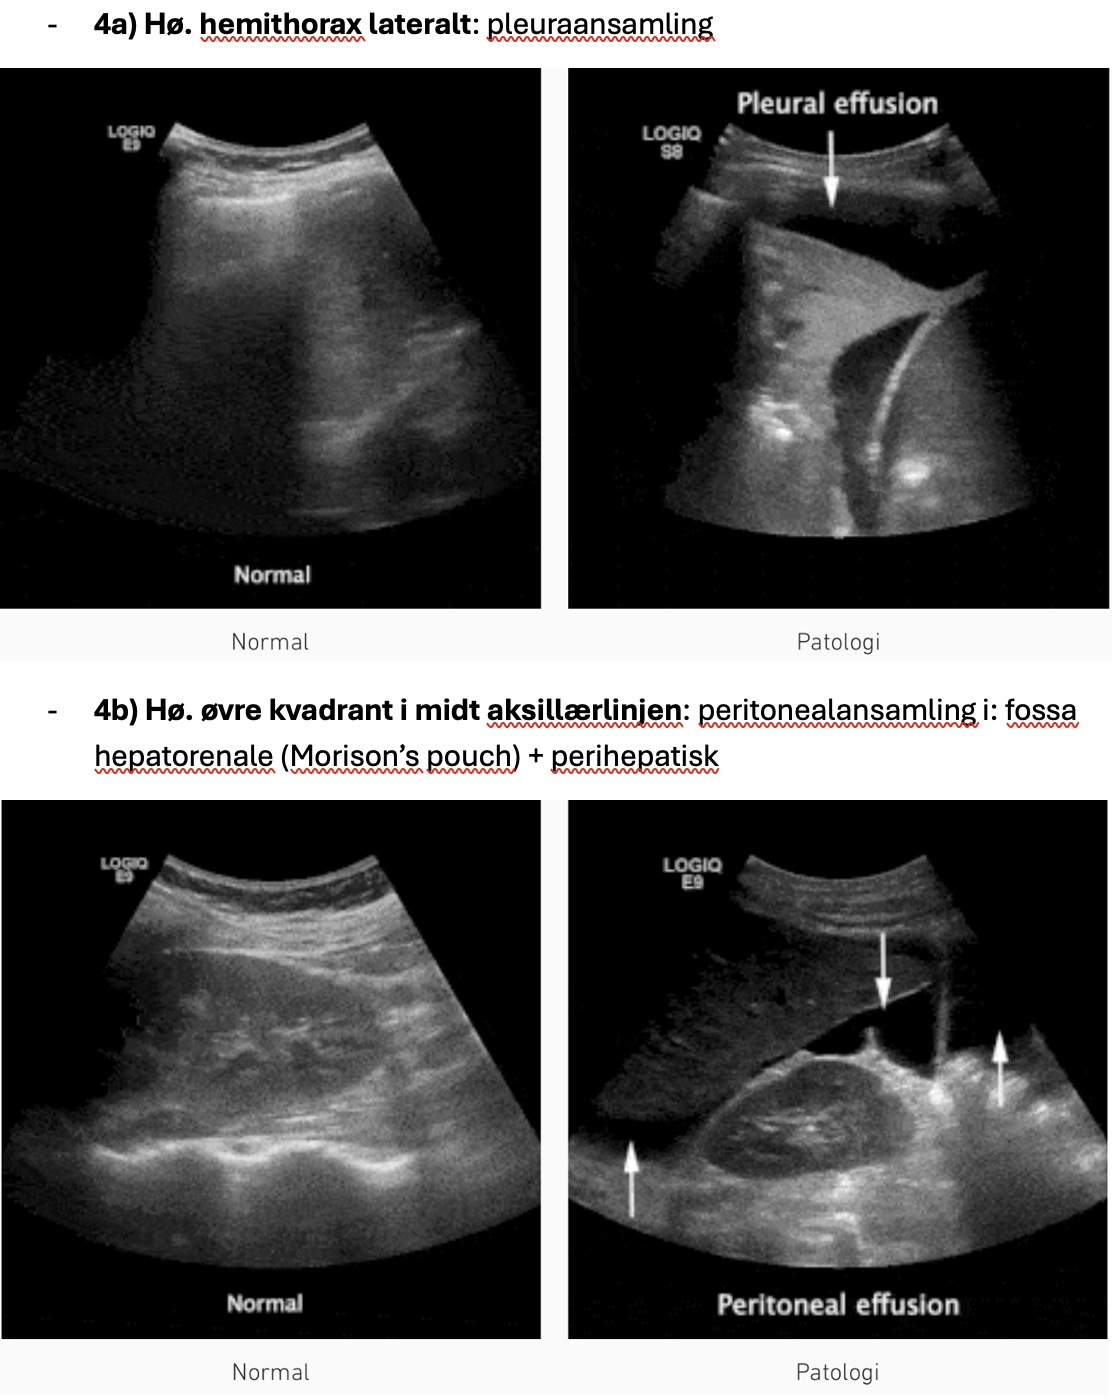

- 4a) Hø. hemithorax lateralt: pleuraansamling

- 4b) Hø. øvre kvadrant i midt aksillærlinjen: peritonealansamling i: fossa hepatorenale (Morison’s pouch) + perihepatisk